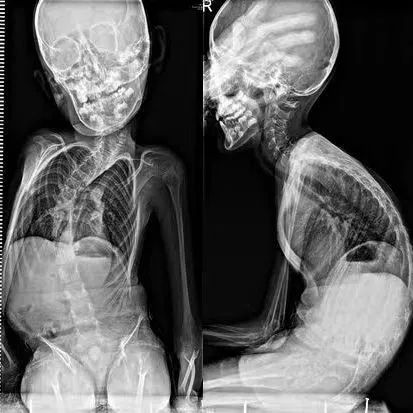

术前、术后CT图

术后的影像学检查提示:维洛的脊柱侧弯从69度变为了术后的10度。坐直以后的维洛身高高了很多,爸爸给他特制的电动轮椅以及家里各种护理用具都要“重新升级”,以适应维洛的新高度。